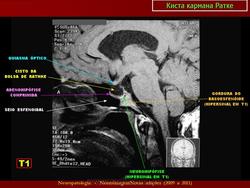

ГМ. Киста кармана Ратке. +

Киста кармана Ратке

Отличные изображения, спасибо. И хорошо что тут стрелочками указана киста и аденогипофиз, который всегда деформирован кистой и киста непосредственно к нему прилижет.

Ратке карман (sacculus hypophysialis; М. Н. Rathke, нем. анатом). Выпячивание эпителия задней стенки ротовой полости зародыша на границе с глоткой; зачаток аденогипофиза. Синоним: гипофизарный карман.